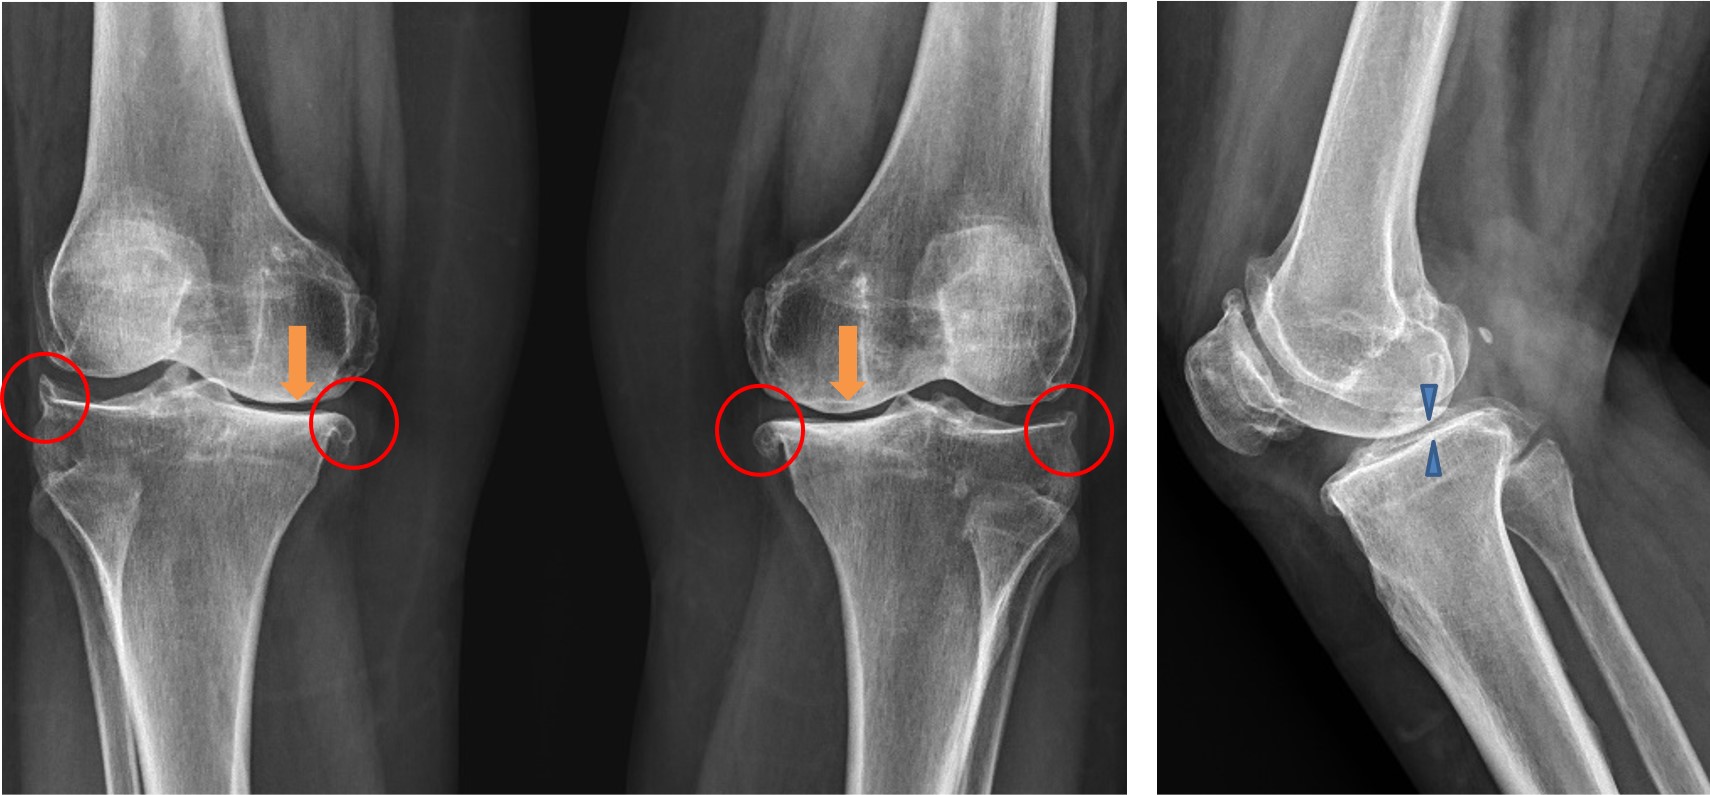

超音波檢查發現尺神經腫脹(圖一),在給予神經解套術與高濃度血小板血漿注射治療後,配合桌椅擺設調整與減少手肘屈曲時間,雙小指麻刺與無力得以緩解。